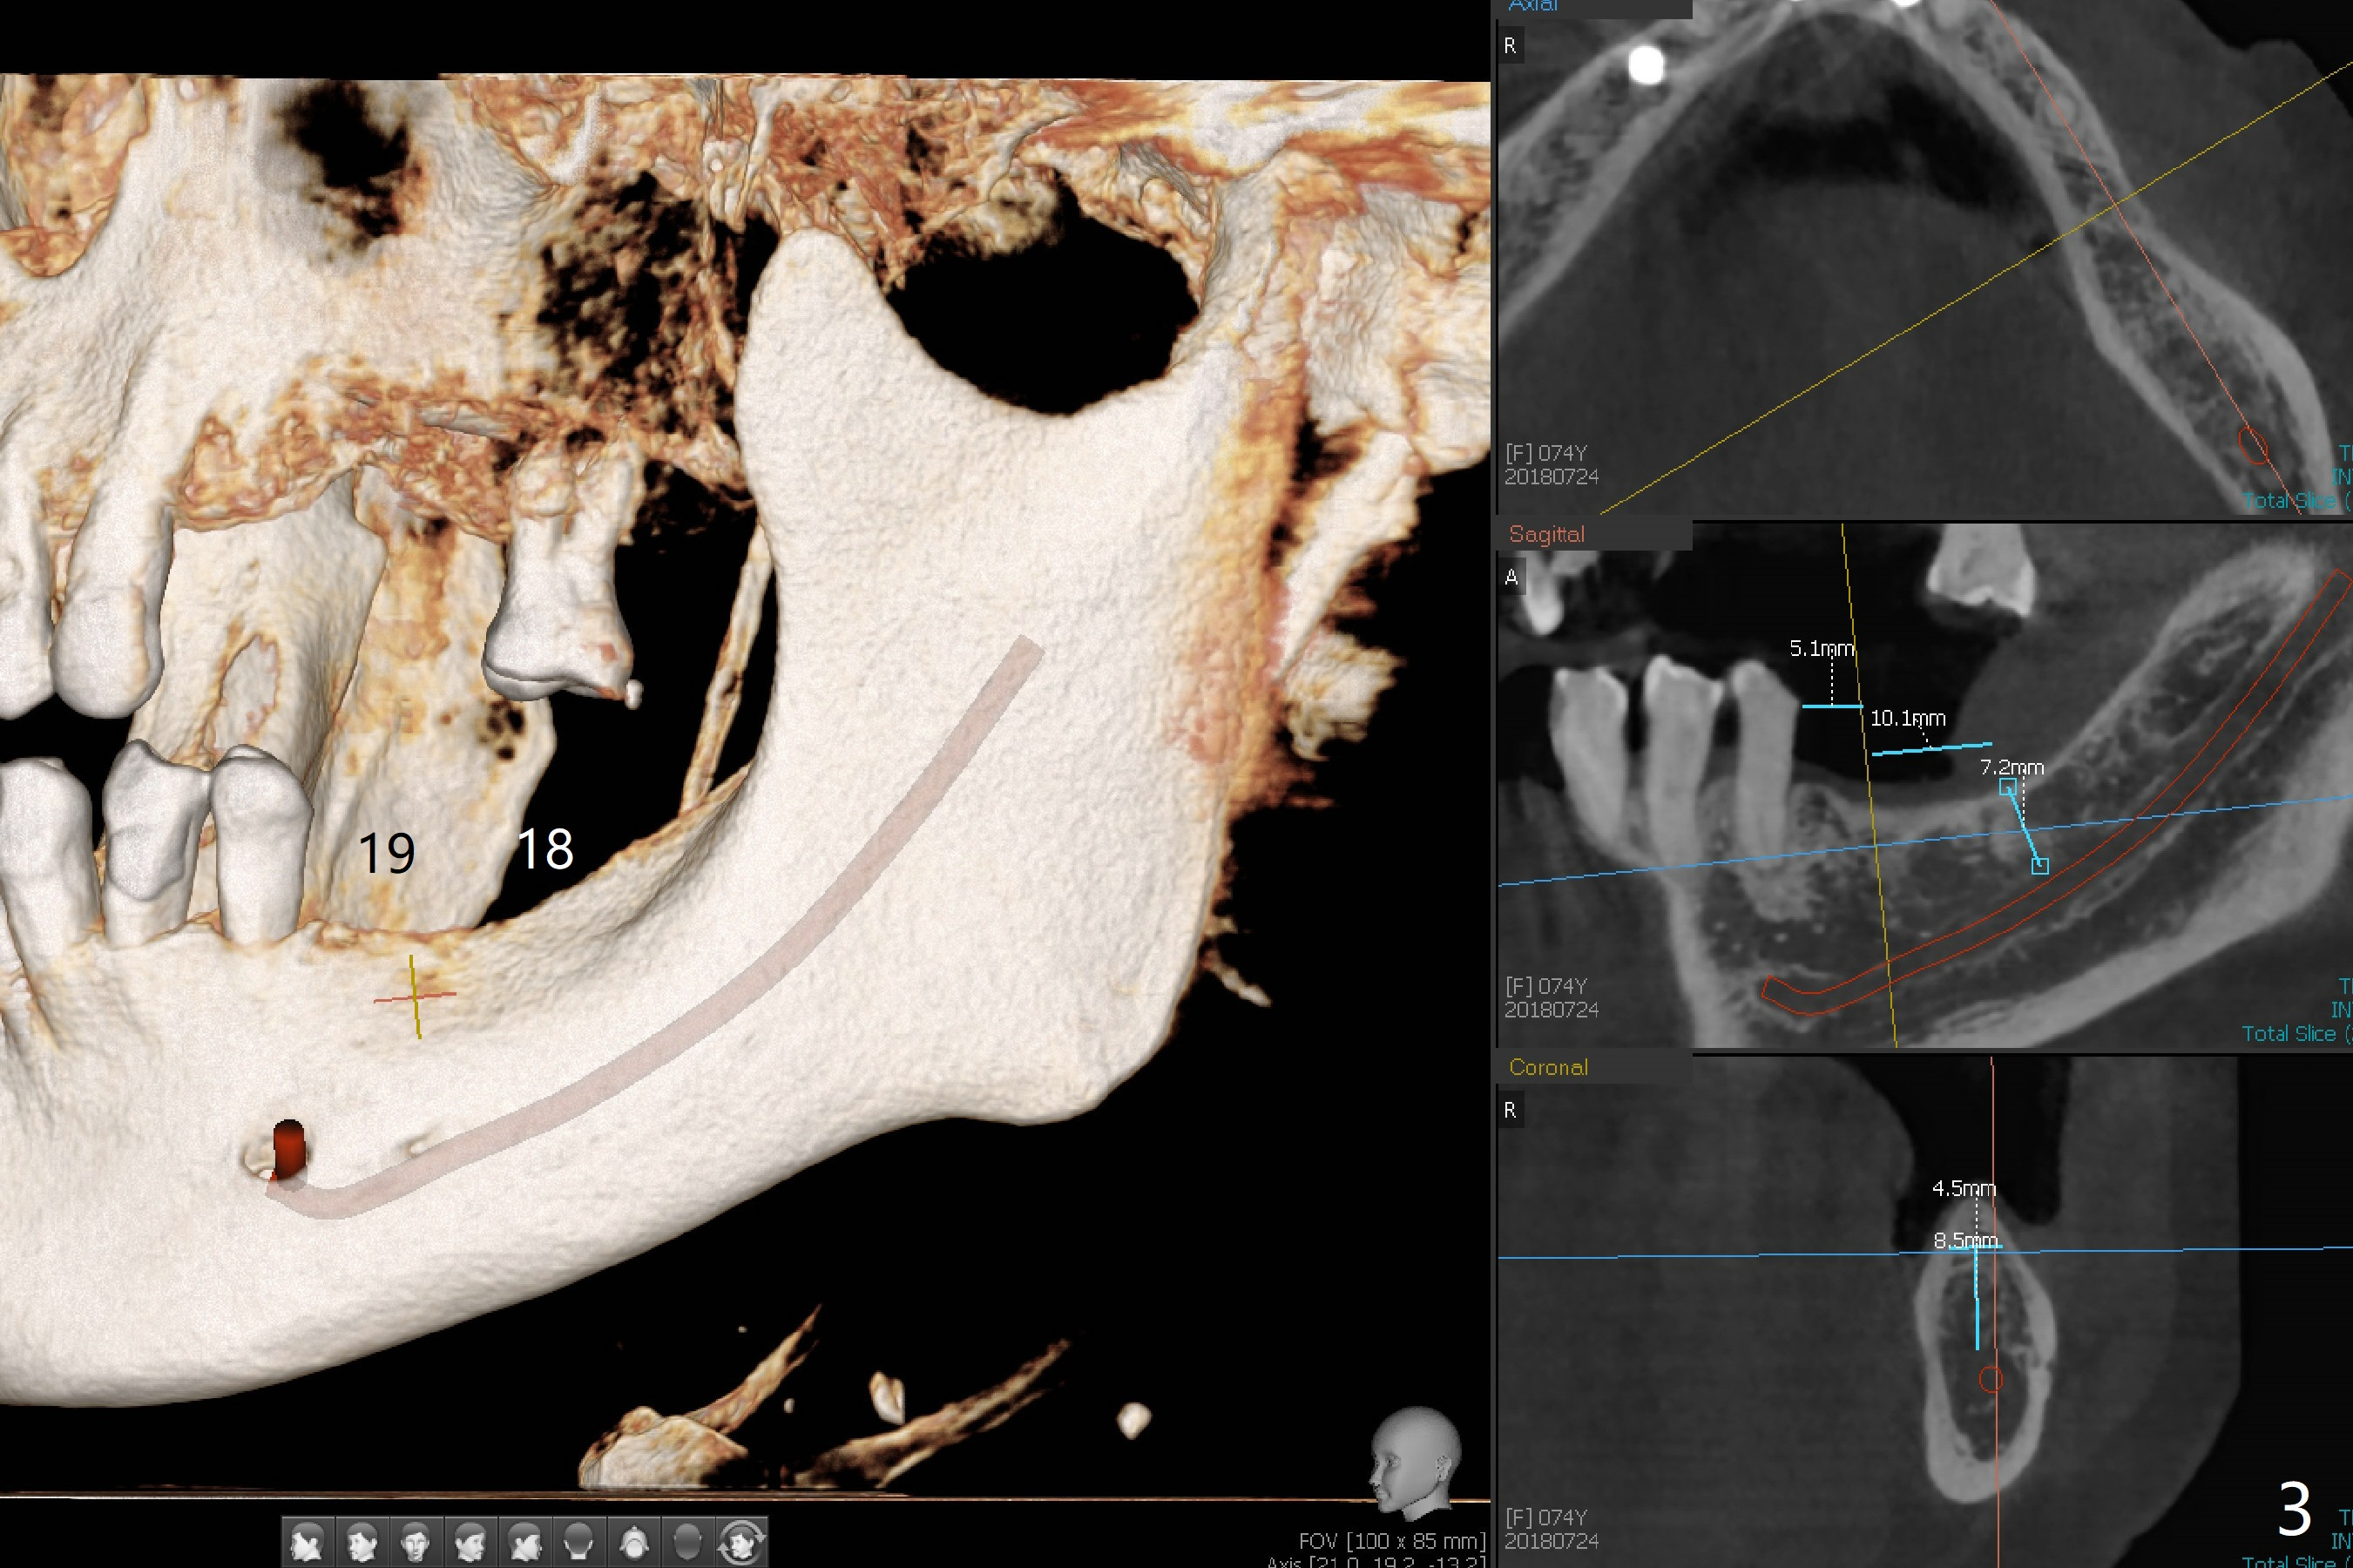

A 74-year-old woman agrees to have implants at #12,14 (for FPD),18 and 19 with guide. Bone height is limited in the molars (Fig.2,3). There is a polyp in the left sinus (Fig.1 *).